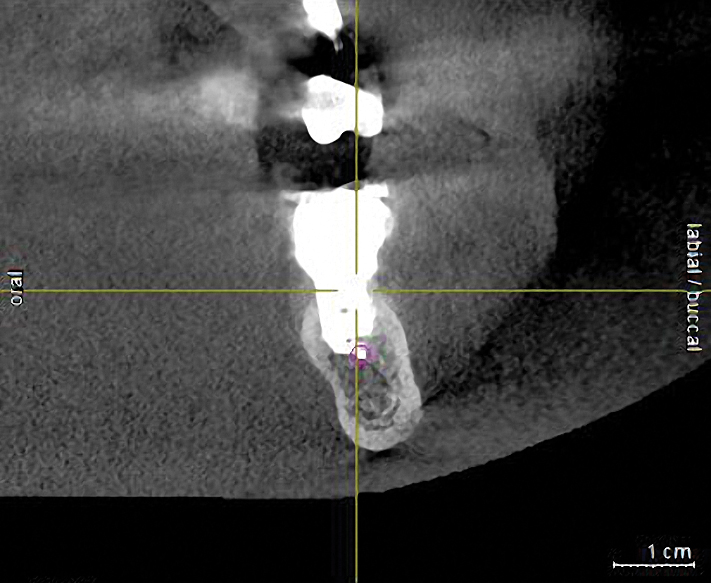

Fig 4. A CT scan was obtained. The scan demonstrated the proximity of the apical lesion to the canal. With proper preoperative planning and imaging, the tooth was successfully removed and the granulomatous tissue carefully debrided without inducing any altered nerve sensation.

Figure 4